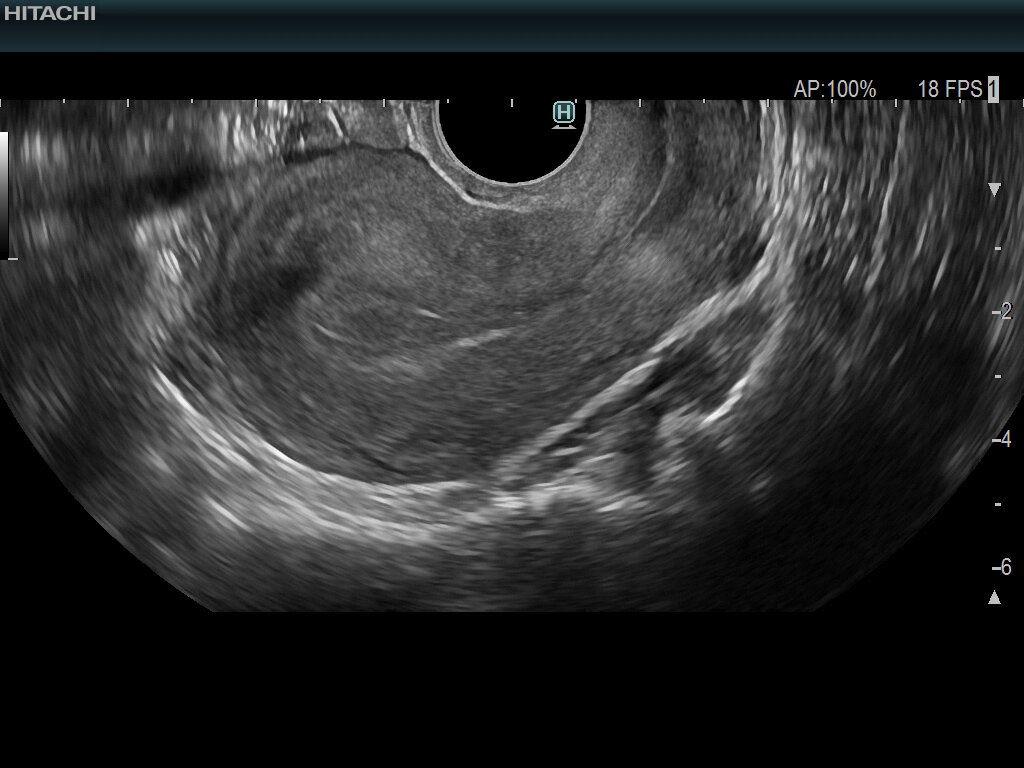

經陰道超音波檢查(依指示排空膀胱)

女性生殖器官,子宮卵巢位於骨盆腔內。若透過腹部超音波,超音波能量經過皮膚、脂肪、肌肉、腸道,會逐漸遞減變弱,能傳達到子宮卵巢再反射回偵測探頭能量相對較低,增加診斷困難度,經陰道檢查超音波探頭可以更深入體內,近距離接觸子宮卵巢,大幅減少能量遞減問題,影像呈現更清晰,提高疾病診察率。

適應對象:早期妊娠、子宮外孕、卵泡監測、骨盆腔腫瘤、子宮內膜評估…

注意事項:探頭每次檢查均會使用全新一次性保險套包覆,使用過即拋棄,無衛生疑慮,無須憋尿脹膀胱。